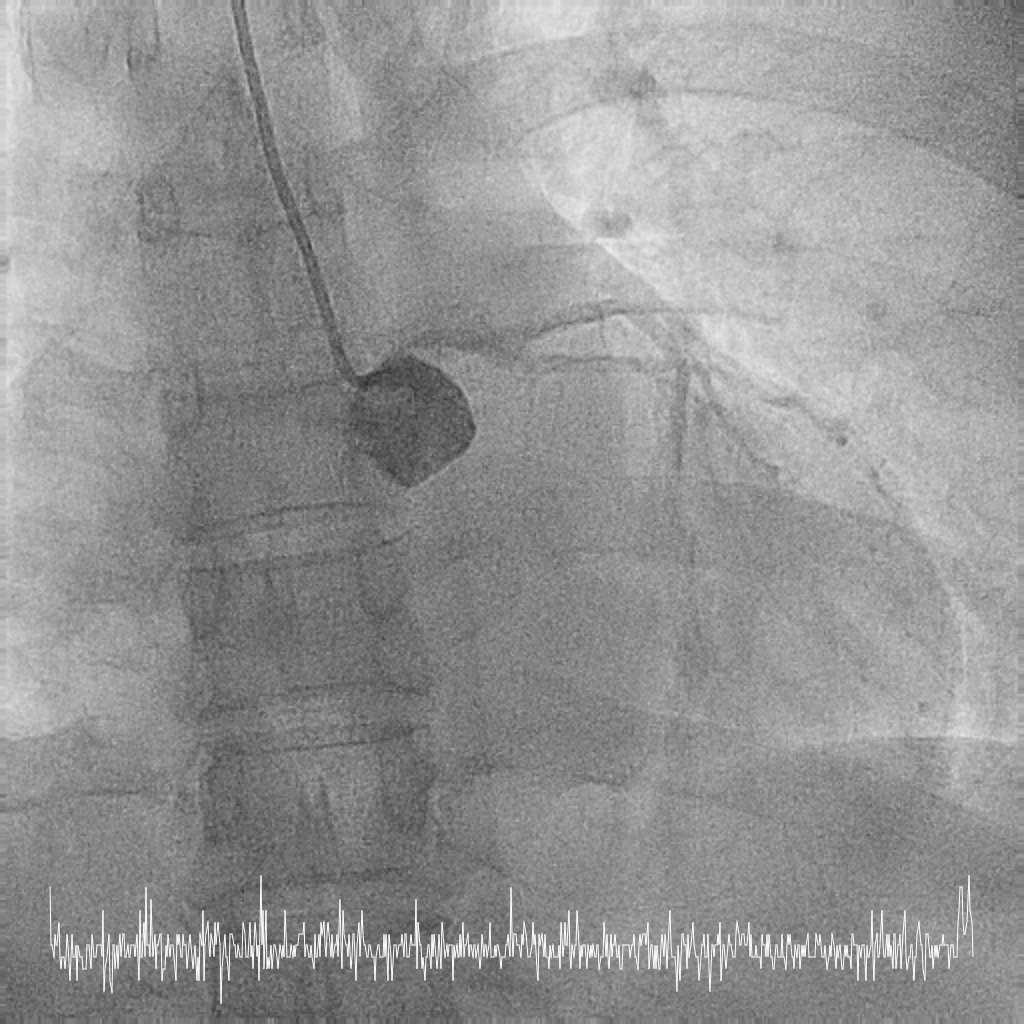

Femoral approach was chosen with a 7F sheath. A 7F JL4 guiding catheter was used for better support. JL4 was not coaxially engaged but positioned close to the ostial LM. Sion Blue ES was wired into LAD from the aortic cusp. A BMW wire was wired into LCx to provide additional support and as a safety wire in case of plaque shift into ostial LCx. Ostial LM was predilated with 3.0/10mm NC balloon at 12ATM which was delivered via Sion Blue ES with the guide and wire floating in the aorta. IVUS after predilatation revealed an ostial LM MLA 5.28mm2 with vessel size 4.0mm. Proximal LAD measured 3.0mm in size and exhibited fibrotic plaque with 70% plaque burden. Both ostial LM and proximal LAD were predilated with 3.0/15mm NC balloon delivered using the floating guide and Sion Blue ES. A 3.0/33mm DES was delivered and deployed with similar technique into proximal LAD using multiple projections for precise positioning to ensure proximal stent edge protrusion of 1-2mm into the aorta. POT of LM and ostial flare were performed using 3.75/15mm NC balloon. Proximal LAD was postdilated with 3.0/15mm NC balloon. IVUS confirmed a well-opposed stent without stent edge dissection. The final ostial LM MSA was 9.7mm2, with stent protrusion (1.7mm) into the aorta (less than one quadrant). The entire ostial LM was covered with stent struts.